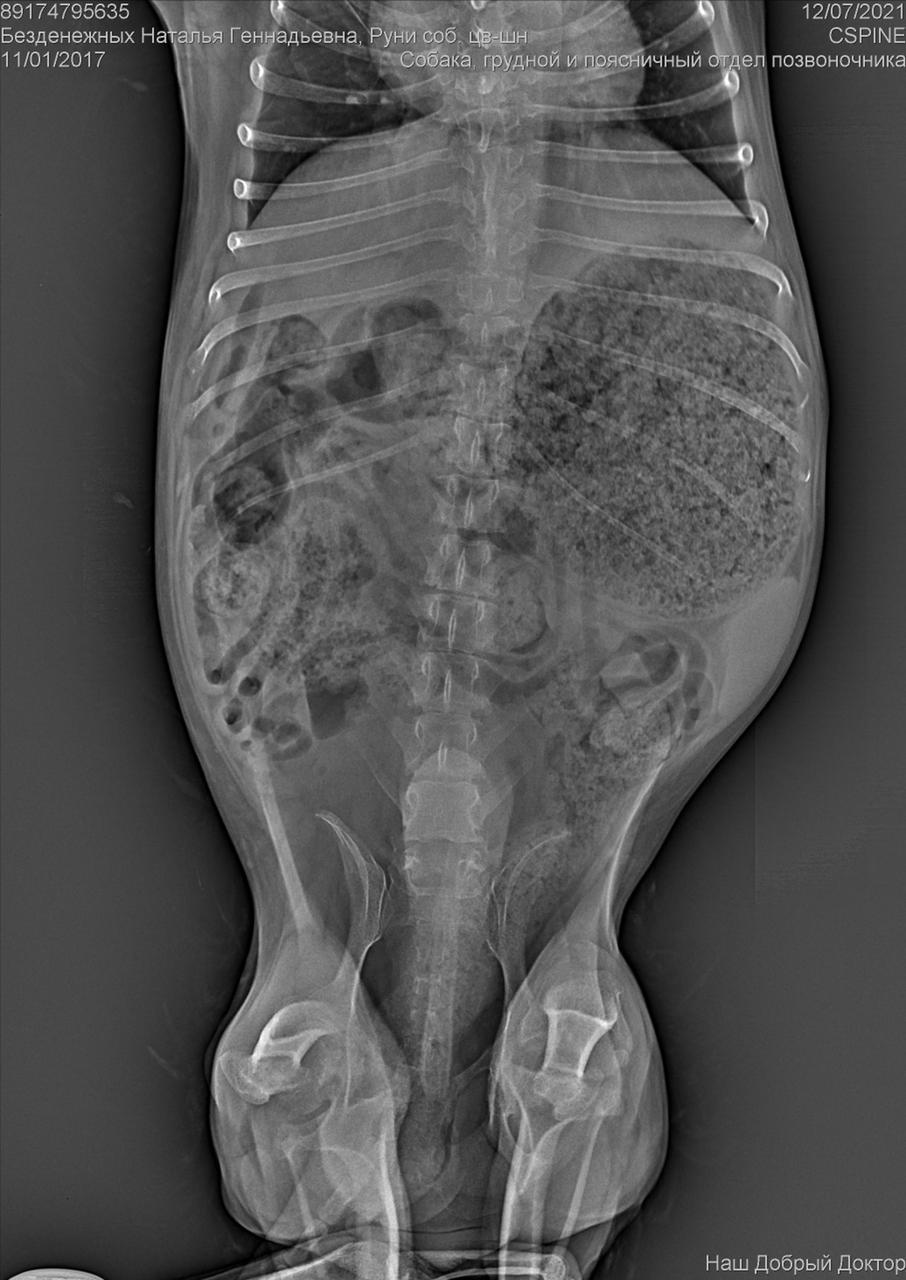

Клиника пообещала отправить рентген на электронку.

Рентген конечно.....

Была травма однозначно. Удалена головка бедра. Мышц нет.

И с позвоночником проблемы. Врачи говорят операции тут не помогут. Если только реабилитация , массаж. Восстановить как то мышцы